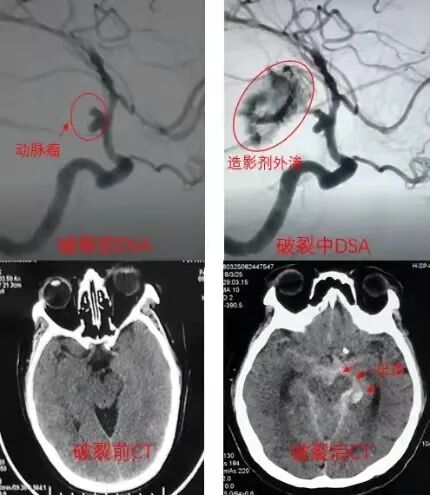

55岁李先生原本是一位健康的公司高管,日前突然发生剧烈头痛、呈爆炸性,伴有呕吐、颈部僵硬等症状,送至医院时肢体无力、反应迟缓,已呈现昏迷状态。头部断层扫描呈现为头部“自发性蛛网膜下腔出血”,CTA结果提示为大脑前交通动脉瘤。幸好,经医师进行紧急介入手术,用弹簧圈成功完全填塞动脉瘤,有效地防止了动脉瘤再度破裂出血,术后经药物及康复治疗李先生恢复良好,出院时四肢活动自如,没有留下任何后遗症。

临床上,蛛网膜下腔出血分为外伤性和自发性两大类。其中,自发性蛛网膜下腔出血是一种常见且致死率极高的疾病,主要以颅内动脉瘤(80%)和脑血管畸形最为常见,其他病因还有高血压性动脉粥样硬化引起的动脉破裂、烟雾病、各种感染引起的脑动脉炎、肿瘤破坏血管等。其中以颅内动脉瘤最为凶险!!!

颅内动脉瘤可分为破裂性和未破裂性;大多数为未破裂的,隐藏于世,如果不做相关体检,就不被人知,甚至其主人也不知道。这时就是一颗“隐形炸弹”。

不过这个病的危害在于:长期隐藏不破则矣,一旦破裂,会导致严重的出血,威胁生命。1/3患者在30天内死亡,1/3患者幸存,但神经功能丧失(残疾),1/3患者康复。动脉瘤破裂一次后,出现再次破裂的机率非常高,不良预后的发生率高达60-70%,因此发生动脉瘤破裂时,一定要即时送医处理。因此本病又被称为“不定时炸弹”。